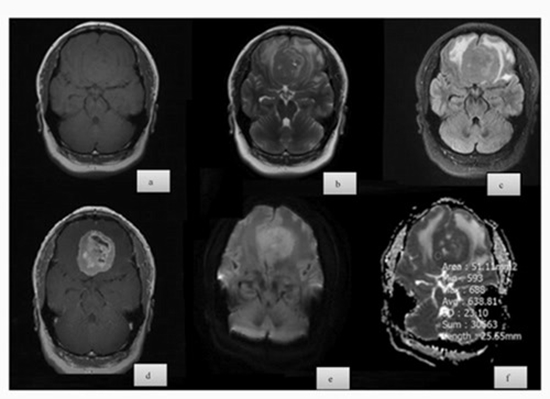

Is There Any Correlation Between Diffusion-Weighted Imaging and Histopathologic Findings of Meningioma? A Retrospective Study

Background and aims: Meningiomas are common CNS tumors, with grading critical for treatment. This study aimed to determine if diffusion-weighted imaging (DWI) correlates with histopathologic findings in meningioma, focusing on tumor grade, subtype, and Ki-67 index.

Methods: This retrospective study included 68 patients with meningioma who underwent preoperative MRI with DWI. Tumor grade was determined using the WHO classification. DWI intensity was categorized as hyperintense, isointense, or hypointense relative to normal brain tissue. ADC values were measured, and diffusion restriction was defined as high signal intensity on DWI with low signal intensity on the ADC map. Histopathologic analysis assessed the Ki-67 proliferation index. Statistical analysis used ANOVA, Chi-square, univariable linear regression (β), and odds ratios (OR) via SPSS 17.0, with p < 0.05 as significant.

Results: The study included 68 patients with a mean age of 52.1 ± 15.6 years, mostly females (67.65%). Most tumors were grade 1 (73.5%) with male patients having higher tumor grades than females. Meningothelial was the most common subtype. DWI intensity correlated with tumor grade, with higher grades more likely to be hypointense. ADC values varied with tumor grades, being significantly higher in grade 1 tumors. Diffusion restriction was more common in higher-grade tumors. Ki-67 was higher in males (p = 0.01) and inversely linked to ADC (p < 0.001).

Conclusion: Both qualitative DWI features and quantitative ADC values reflect meningioma grade and proliferative activity, with notable sex and subtype differences, underscoring the clinical utility of preoperative DWI